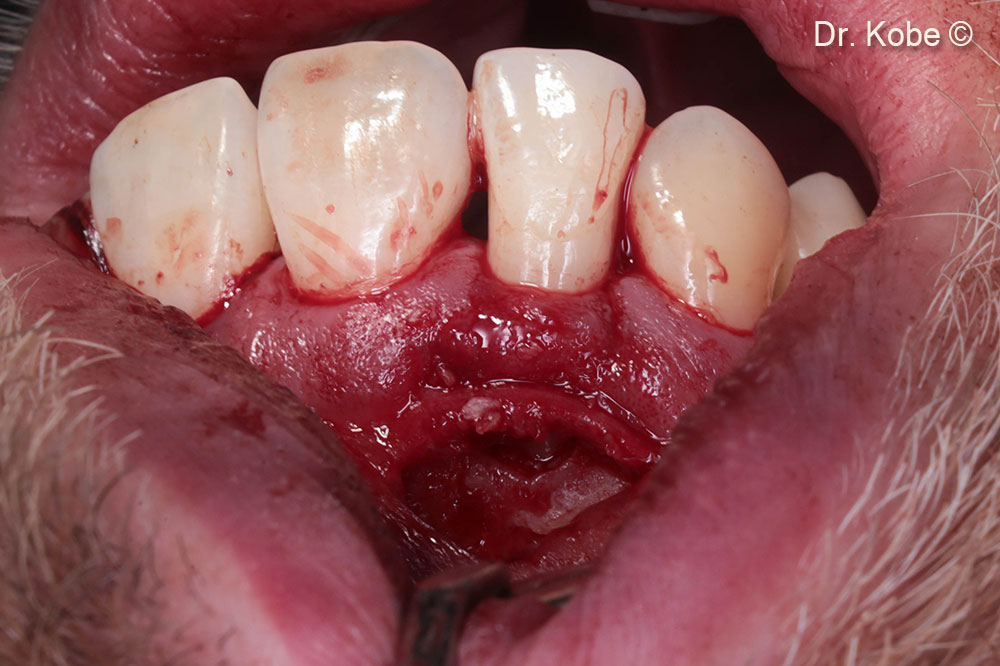

Horizontal incision (NIPSA) in the vestibule

Access to the defect